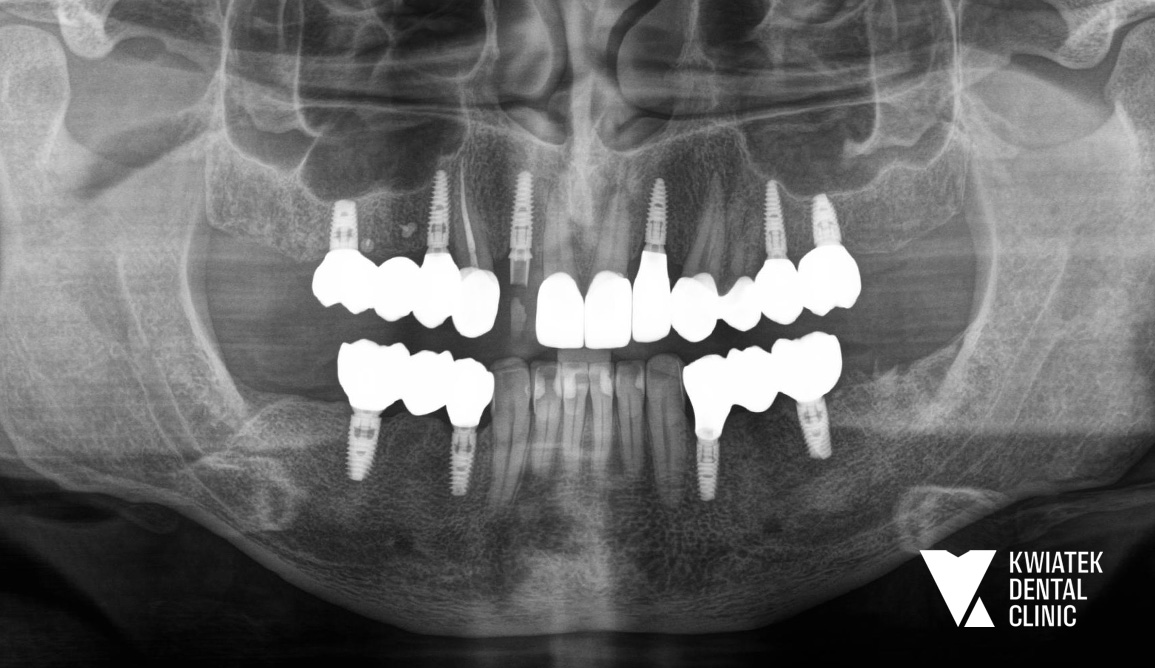

PO

W kolejnym etapie usunięto ósemki, a po wygojeniu tkanek wykonano skany cyfrowe i rejestrację zwarcia, aby precyzyjnie zaplanować rozmieszczenie implantów i kształt przyszłych koron. Podczas zabiegów zastosowano szablony chirurgiczne, co pozwoliło bezpiecznie i precyzyjnie wszczepić implanty zębowe.

Po integracji implantów wykonano korony ceramiczne na implantach oraz korony pełnoceramiczne na zębach własnych, dzięki czemu cały uśmiech zyskał harmonijny, estetyczny wygląd.

Leczenie zakończyliśmy instruktażem higieny, profesjonalną kontrolą okluzji i zaleceniem regularnych wizyt higienizacyjnych co 6 miesięcy.